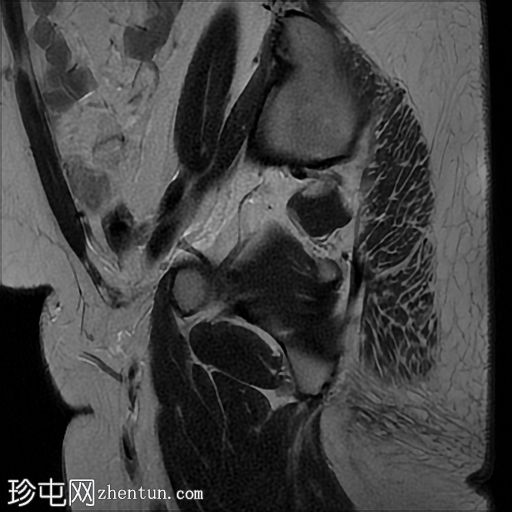

矢状位

T2加权像

左侧卵巢增大,呈弥漫性低T1信号和高T2信号,可见周边卵泡,部分卵泡除周边卵泡周围有环状强化外,无明显实质强化。左侧附件蒂呈漩涡状,提示卵巢扭转。